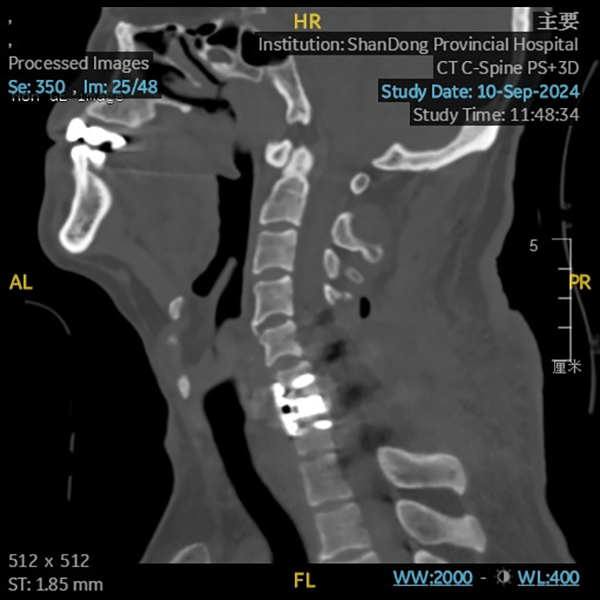

9月11日,创伤中心专家团队为患者实施了二期手术。主任医师周东生、张鹏带领专家团队为患者实施了颈椎前路椎间盘切除减压椎体融合手术。手术采用颈前右侧横切口,暴露定位C6/C7,切除破损椎间盘及C7游离骨块,进行彻底椎管减压。后续植入椎间融合器(Cage),安装前路钛板,进行椎间融合固定。二期手术历时1.5小时,患者苏醒后肢体活动同术前。术后行颈椎CT+三维重建检查显示脱位椎体已经完全复位,颈椎序列良好,脊髓神经功能得到完全保留。